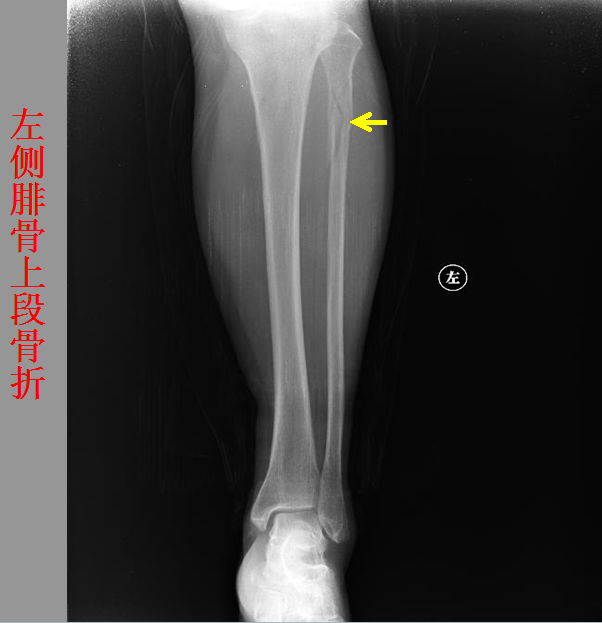

骨折篇

01

定义:骨折{Fracture}是指骨的完整性和连续性的折裂或粉碎。包括创伤性骨折、疲劳性骨折和病例理性骨折。 临床上以创伤性骨折*常见。